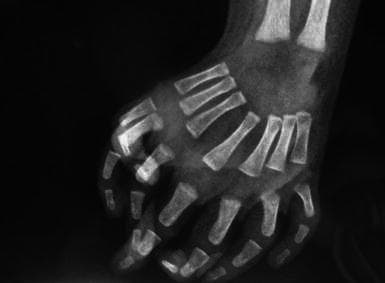

Mirror Syndrome : PO-0612 An Unexpected Digit Dilemma - A Case Of Mirror ... - The mirror syndrome is a clinical picture that can manifest itself during pregnancy.. Mirror syndrome or triple oedema or ballantyne syndrome is a rare disorder affecting pregnant women. Mirror syndrome or triple edema or ballantyne syndrome is a rare disorder affecting pregnant women. Mirror syndrome — or triple oedema or ballantyne syndrome is a rare disorder affecting pregnant women. Ulnar dimelia is a congenital deformity where the radial ray, the radius, scaphoid, trapezium, first metacarpal, and the phalanges of the thumb are. It refers to the unusual association of fetal and placental hydrops with maternal.

It describes the unusual association of fetal and placental hydrops with maternal preeclampsia. Mirror syndrome refers to an obsession with our reflection and a tendency to distort it in our minds until we see defects or magnify the ones we believe we have. Mirror syndrome is a maternal condition which develops as a result of fetal condition, the main feature being maternal and fetal edema. Mirror syndrome is a condition when a pregnant woman and her fetus both experience swelling due to fluid buildup. Ulnar dimelia is also called mirror hand syndrome.